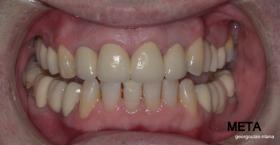

ΠΡΟΣΘΕΤΙΚΗ ΑΠΟΚΑΤΑΣΤΑΣΗ ΣΤΗΝ ΑΝΩ Κ ΚΑΤΩ ΓΝΑΘΟ ΚΑΙ ΤΟΠΟΘΕΤΗΣΗ ΕΜΦΥΤΕΥΜΑΤΩΝ ΜΕ ΚΛΕΙΣΤΗ ΑΝΥΨΩΣΗ ΙΓΜΟΡΕΙΟΥ

Ο ασθενής  προσήλθε στο ιατρείο μας θέλοντας να βελτιώσει την εμφάνιση των πρόσθιων δοντιών του και να αποκαταστήσει την υγεία κ την λειτουργία όλου του στόματος. Πραγματοποιήθηκε περιοδοντική θεραπεία κ ενδοδοντικές θεραπείες (απονευρώσεις) όπου κρίθηκε απαραίτητο και στη συνέχεια τοποθετήθηκαν 3 εμφυτεύματα, 2 δεξιά στις θέσεις του πρώτου κ δεύτερου γομφίου κ 1 αριστερά στη θέση του πρώτου προγομφίου. Κατά την  τοποθέτηση των 2 εμφυτευμάτων της δεξιάς πλευράς, πραγματοποιήθηκε κλειστή ανύψωση ιγμορείου με το σύστημα Piezotome-Intralift , τεχνική που εξασφαλίζει τη μικρότερη δυνατή επέμβαση κ τη μικρότερη μετεγχειρητική ταλαιπωρία (minimally invasive), καθώς κ αυξητικους παράγοντες PRF. Σε όλη τη διάρκεια της θεραπείας  ο ασθενής ήταν καλυμμένος τόσο αισθητικά όσο και λειτουργικά με προσωρινές μεταβατικές αποκαταστάσεις. 4 μήνες μετά την  τοποθέτηση των εμφυτευμάτων κ την οστεοενσωμάτωσή τους, ακολούθησε η τοποθέτηση των μόνιμων αποκαταστάσεων.